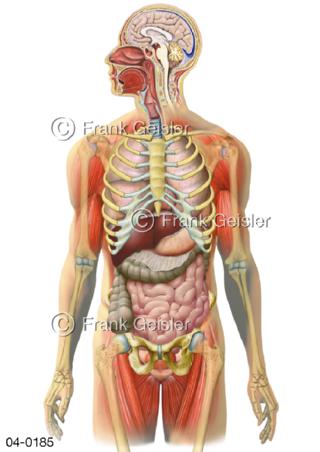

Bildergalerie Topografie Organe

Bilder zur topografischen Anatomie, die Lage der Organe und die Strukturen nach ihren räumlichen Lagebeziehungen zueinander, Übersicht der inneren Organe im Kopf und im Rumpf, Topografie der Organe im Brustraum (Thorax) und im Bauchraum (Abdomen)